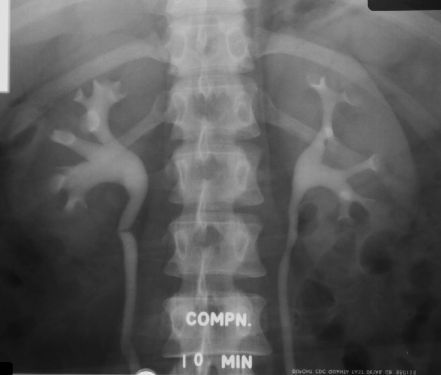

- IVP, MCU, ASU